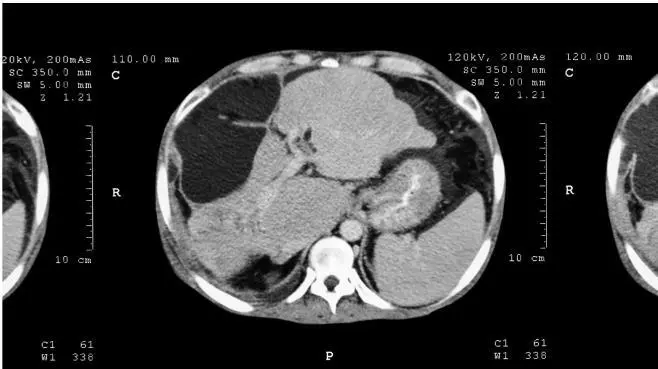

Большинство болезней печени приводит к тому, что клетки печени и печеночные дольки умирают. А поскольку печень является органом однородным, то все эти изменения происходят равномерно по всему органу. Одна клетка в левой части печени погибла, одна – в правой, одна – посередине, другие несколько клеток погибли в верхней части печени, еще несколько – в нижней части. В итоге получается картинка, похожая на мозаику. Если посмотреть на печень, то она в результате практически любой болезни становится не идеально гладкой, как была раньше, а приобретает диффузные, или размазанные, изменения. Выглядит это как рябь на воде или помехи на черно-белом телевизоре, такие «мурашки». Это типичные изменения в печени при всех воспалительных и большинстве инфекционных заболеваний. Их и называют диффузными изменениями печени в противоположность очаговым. Смотрите на рис. 60.

Рис. 60. Диффузные и очаговые изменения печени на КТ

Очаговые изменения в печени предполагают в первую очередь наличие некоего локального очага, то есть отдельно расположенного совсем другого участка внутри или на поверхности печени. И именно такие измененные участки, или очаги, вызывают множество вопросов и дают поводы для опасений и тревожности. Локальные, или очаговые, изменения еще называют образованиями печени. Но не торопитесь: не от слова «онкология», а от слова «образовалось». То есть в печени что-то образовалось. Однако если бы вы прочитали результаты многих УЗИ печени, то с удивлением обнаружили бы скудный ассортимент диагнозов. Там можно увидеть в основном только два варианта: либо это киста, либо гемангиома. Так ли это на самом деле?